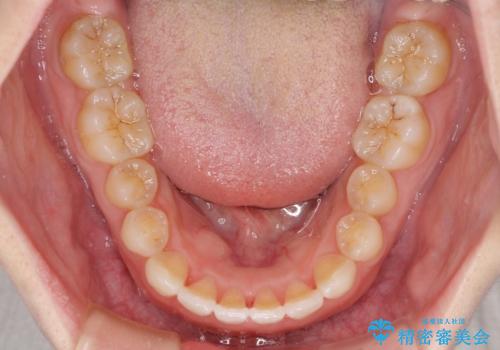

1日22時間の装着時間をしっかり守ってくださったので、1年程度で治療を終えることができました。

1セットのマウスピースで概ね治療を終えたのですが、前歯僅かな叢生が残ったため、2セット目のマウスピースで仕上げました。

気にしていた口元の印象が改善され、患者様には大変満足していただきました。